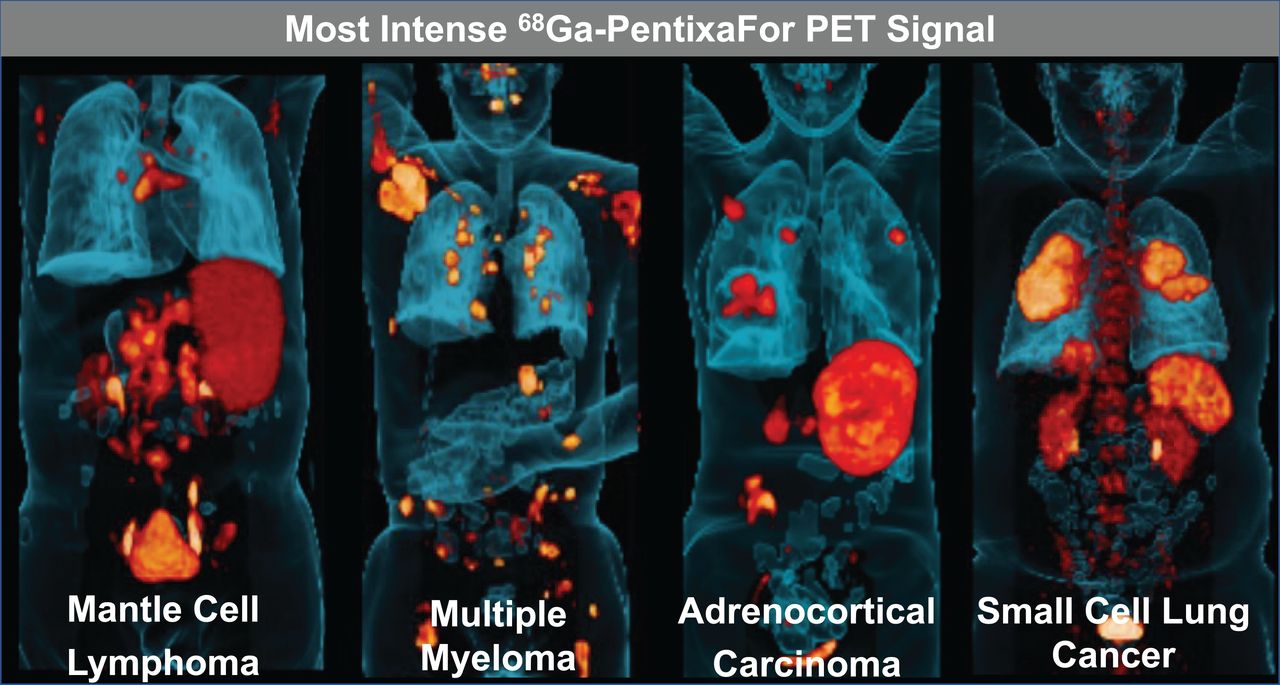

Molecular Imaging for Integrat Tamaki, Nagara; Kuge, Yuji 18F-Fluorodeoxyglucose Imaging for Assessing Cardiovascularの詳細情報

18F-Fluorodeoxyglucose Imaging for Assessing Cardiovascular。Imaging of C-X-C Motif Chemokine Receptor 4 Expression in。Synthesis, preclinical, and initial clinical evaluation of。

MolecularImagingforIntegrat

MolecularImagingforIntegrat